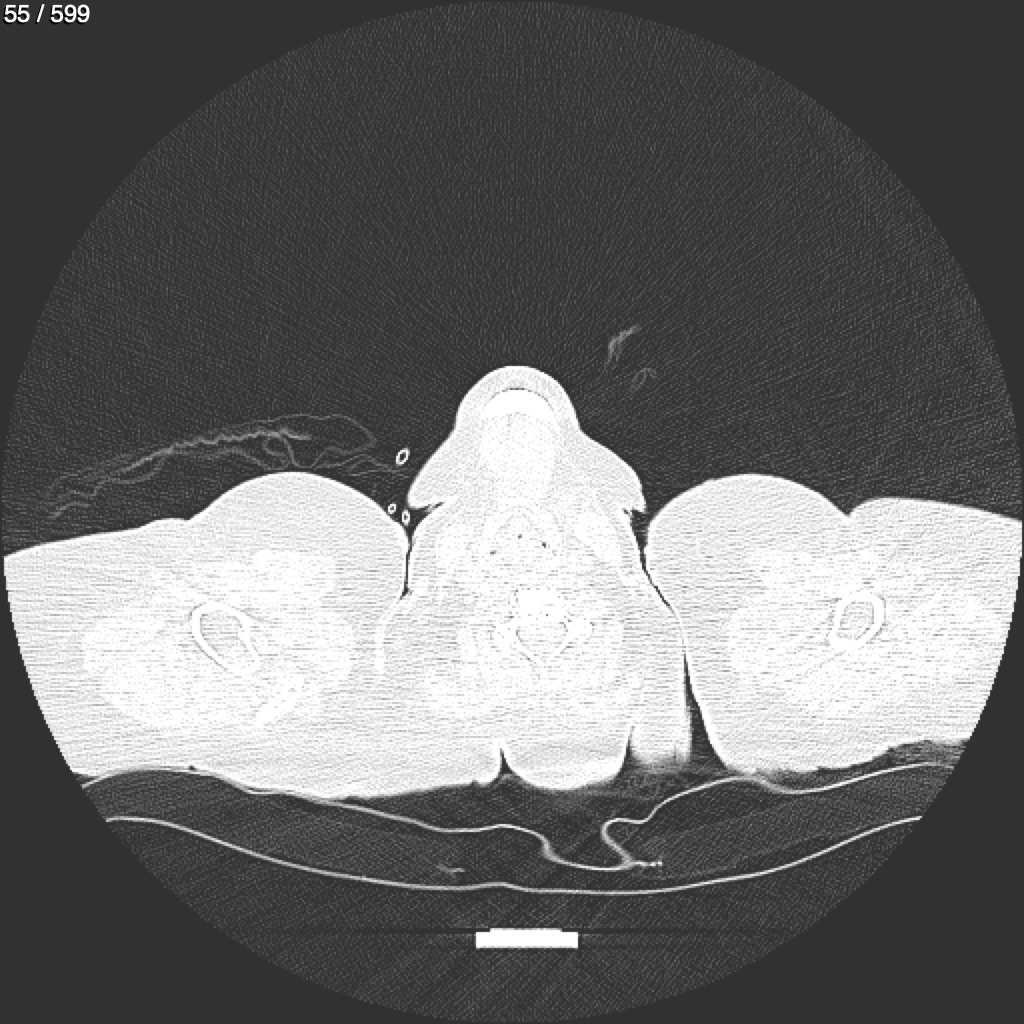

Home G​l​o​r​i​a​ ​G​l​a​d​y​s​ ​B​e​a​s​l​e​y​ ​-​ ​T​ó​r​a​x​ ​T​o​r​a​x​_​S​i​m​p​l​e​ ​(​A​d​u​l​t​o​)